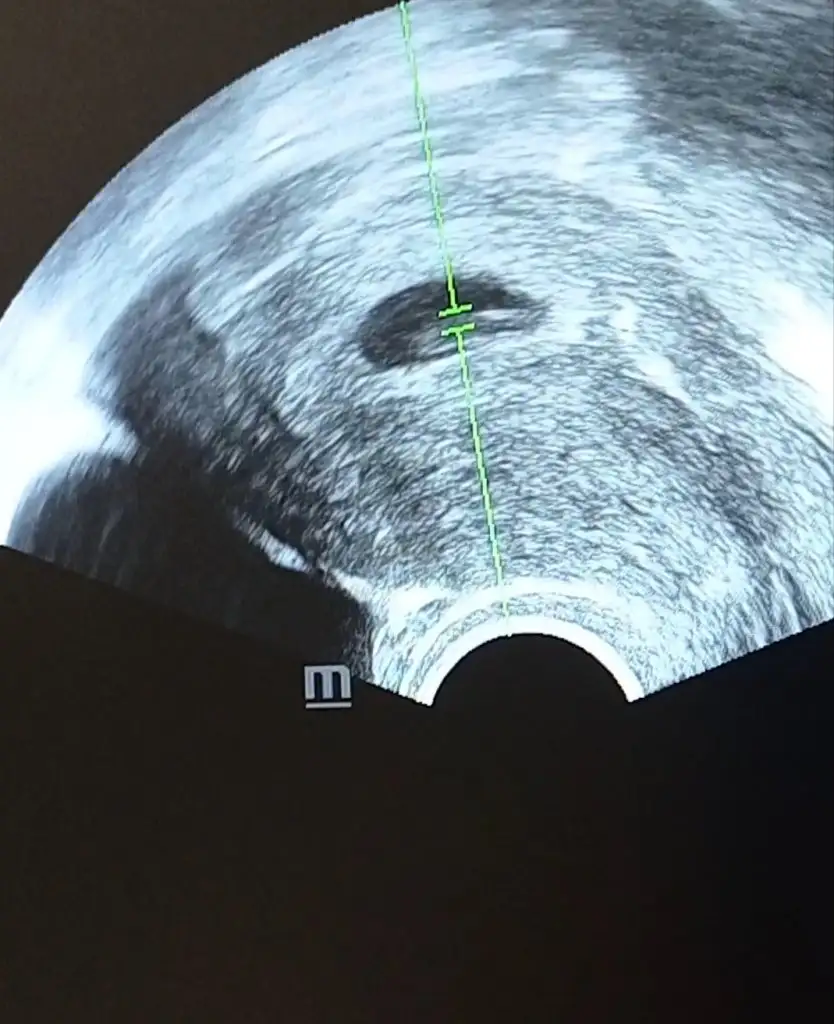

Ikra meyra Merhabaaa benim minnakım 12 haftalik oldu. doktor bisey soylemedi yorum dahi yapmadi . Acaba banada bi tahmin soyleyebilir misiniz Ikra meyra

Eklentiler

• 20210707_062826.webp

29,2 KB · Görüntüleme: 77

• 20210707_062820.webp

31,9 KB · Görüntüleme: 81